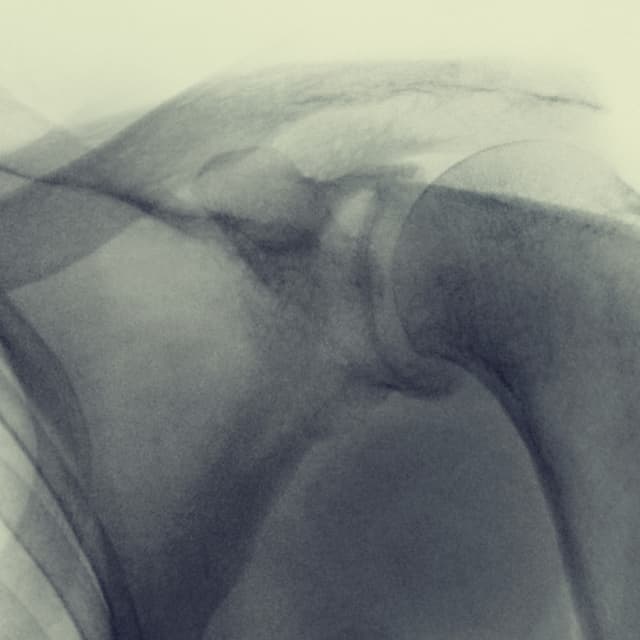

Shoulder Arthroscopy

Shoulder arthroscopy is a minimally invasive surgical procedure used for diagnosing and treating problems with in the shoulder joint. Imagine a tiny camera the size of a pencil! That's the arthroscope, which surgeons insert through a small incisions in your skin to view the joint on a screen.